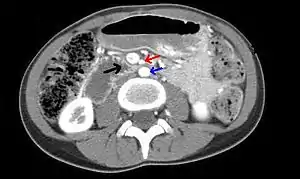

| Abdominal and pelvic computed tomography scan showing duodenal compression (black arrow) by the superior mesenteric artery (red arrow) and the abdominal aorta (blue arrow). | |

Diagnosis is very difficult, and usually one of exclusion. SMA syndrome is thus considered only after patients have undergone an extensive evaluation of their gastrointestinal tract including upper endoscopy, and evaluation for various malabsorptive, ulcerative and inflammatory intestinal conditions with a higher diagnostic frequency. Diagnosis may follow X-ray examination revealing duodenal dilation followed by abrupt constriction proximal to the overlying SMA, as well as a delay in transit of four to six hours through the gastroduodenal region. Standard diagnostic exams include abdominal and pelvic computed tomography (CT) scan with oral and IV contrast, upper gastrointestinal series (UGI), and, for equivocal cases, hypotonic duodenography. In addition, vascular imaging studies such as ultrasound and contrast angiography may be used to indicate increased bloodflow velocity through the SMA or a narrowed SMA angle.[12][13]